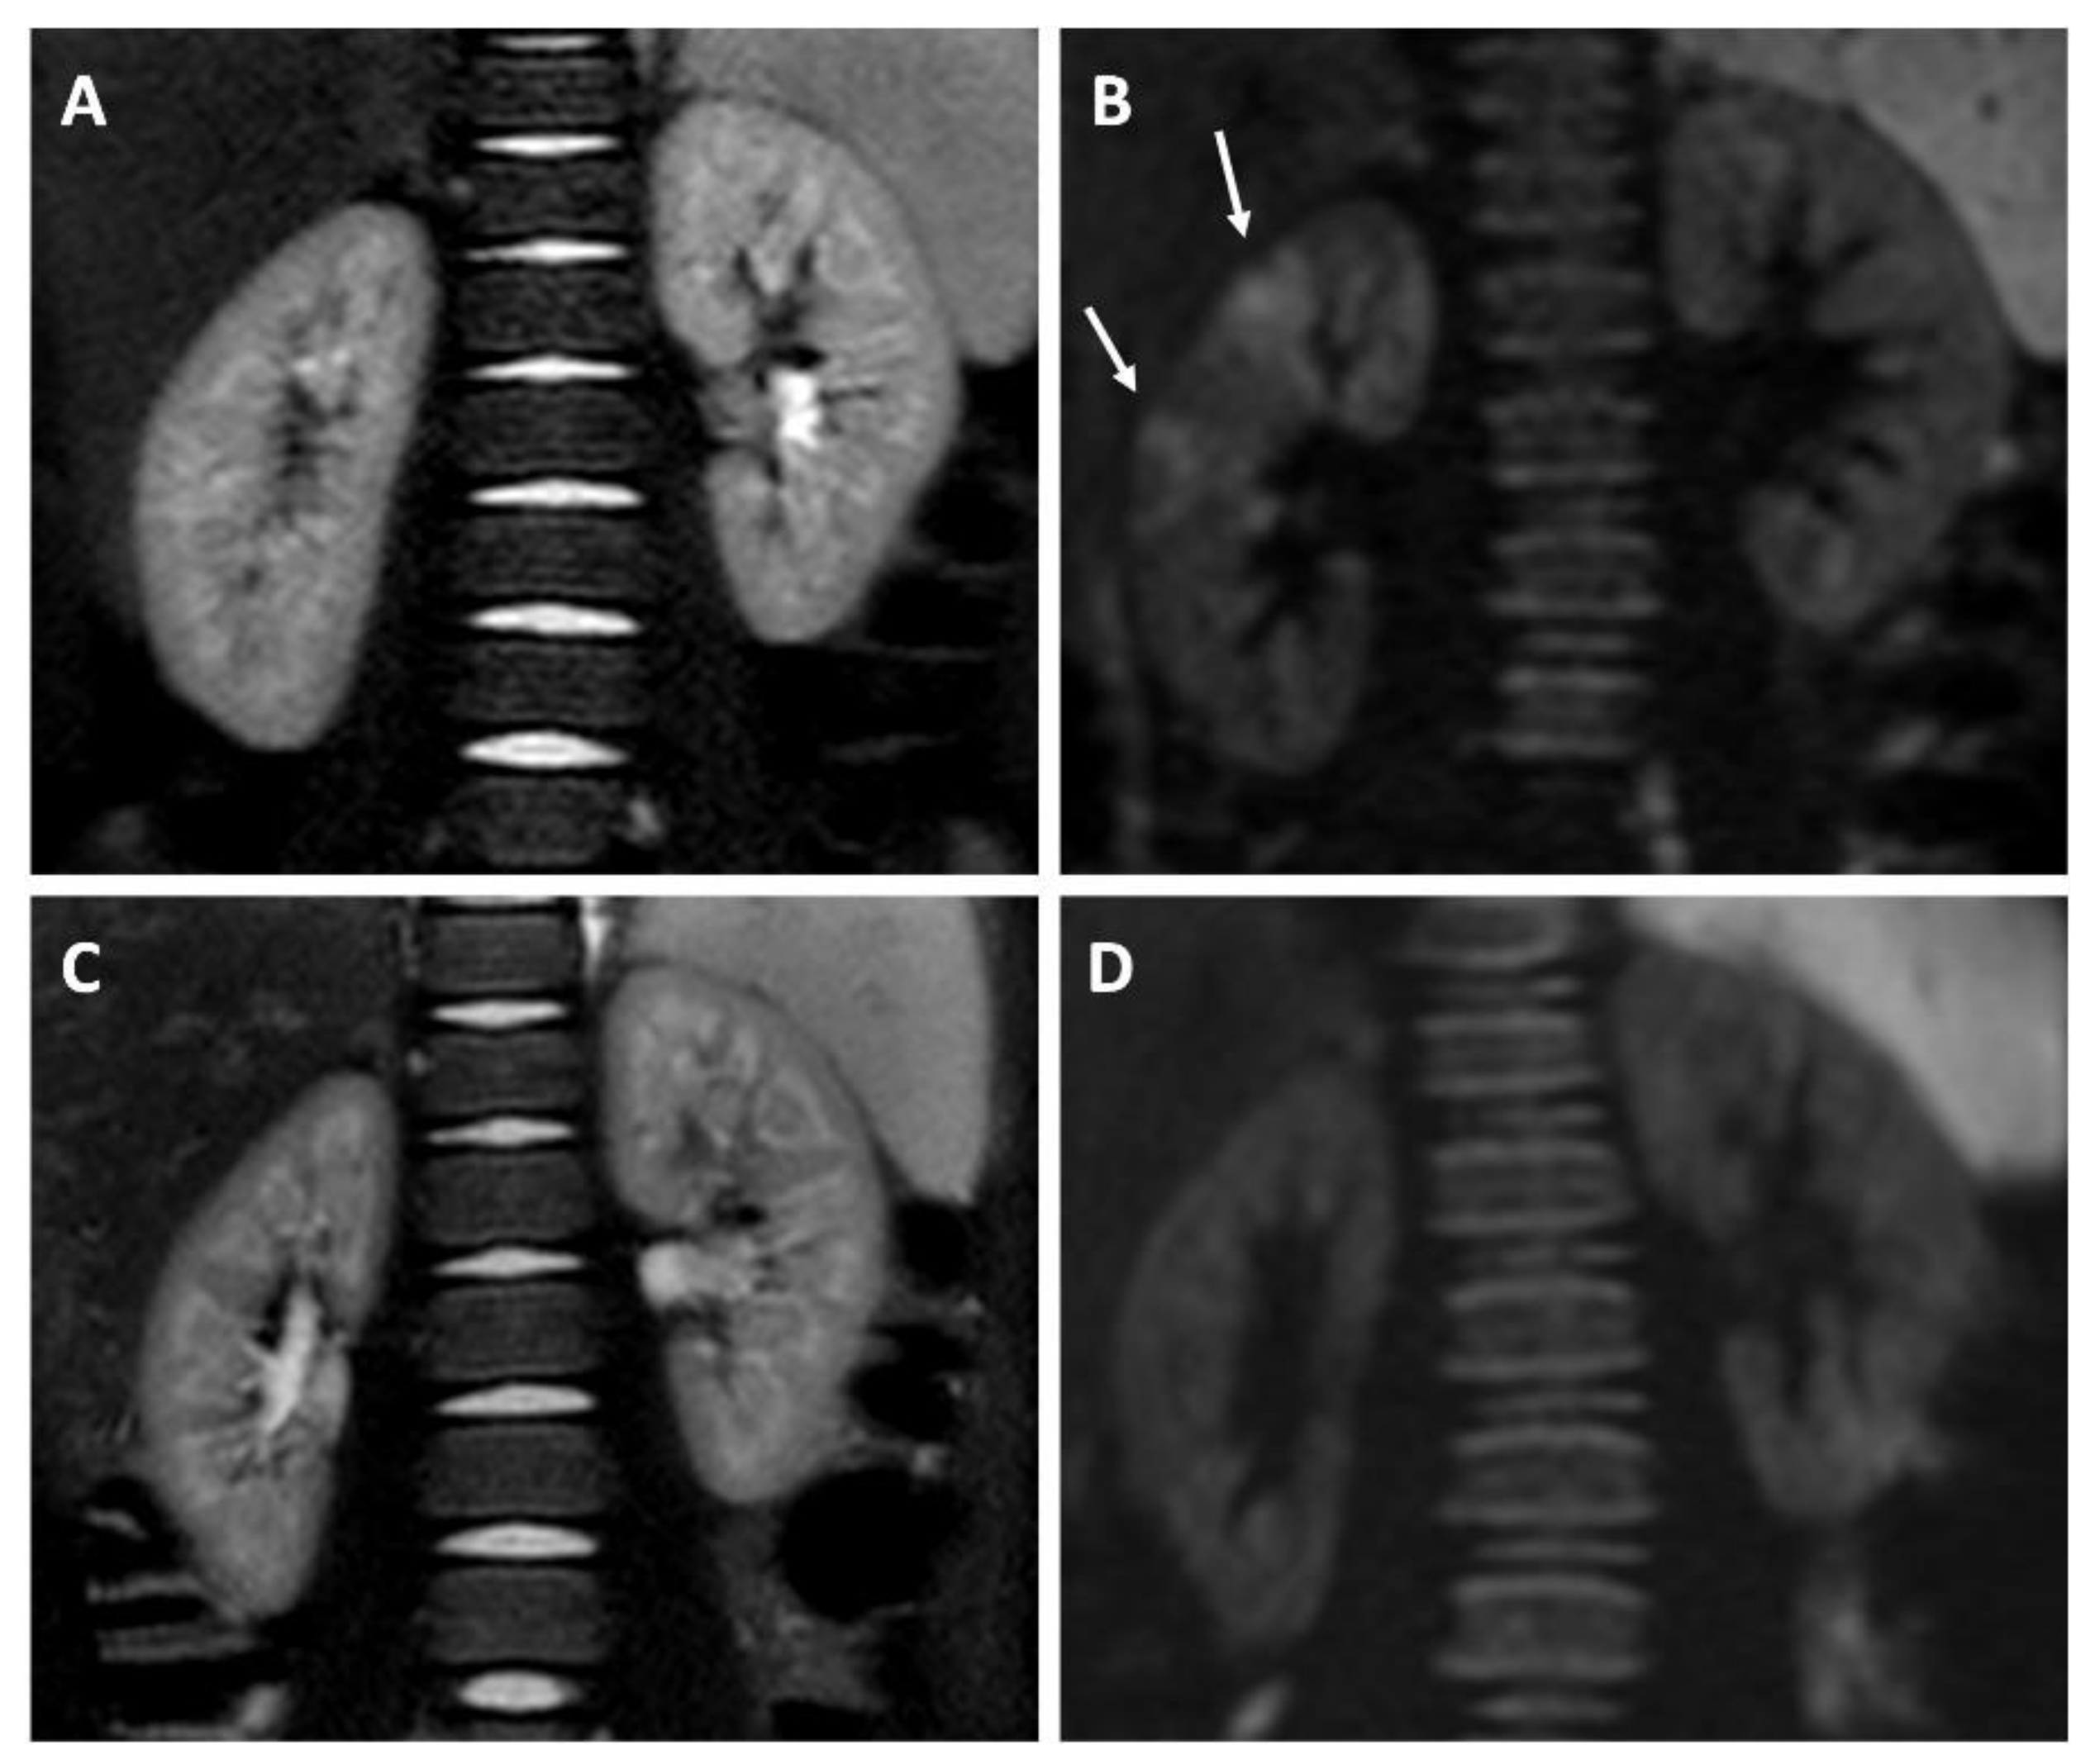

- Focal parenchymal areas with restricted diffusion;

- Seat, number, and mono- or bi-laterality of the focal renal lesions.